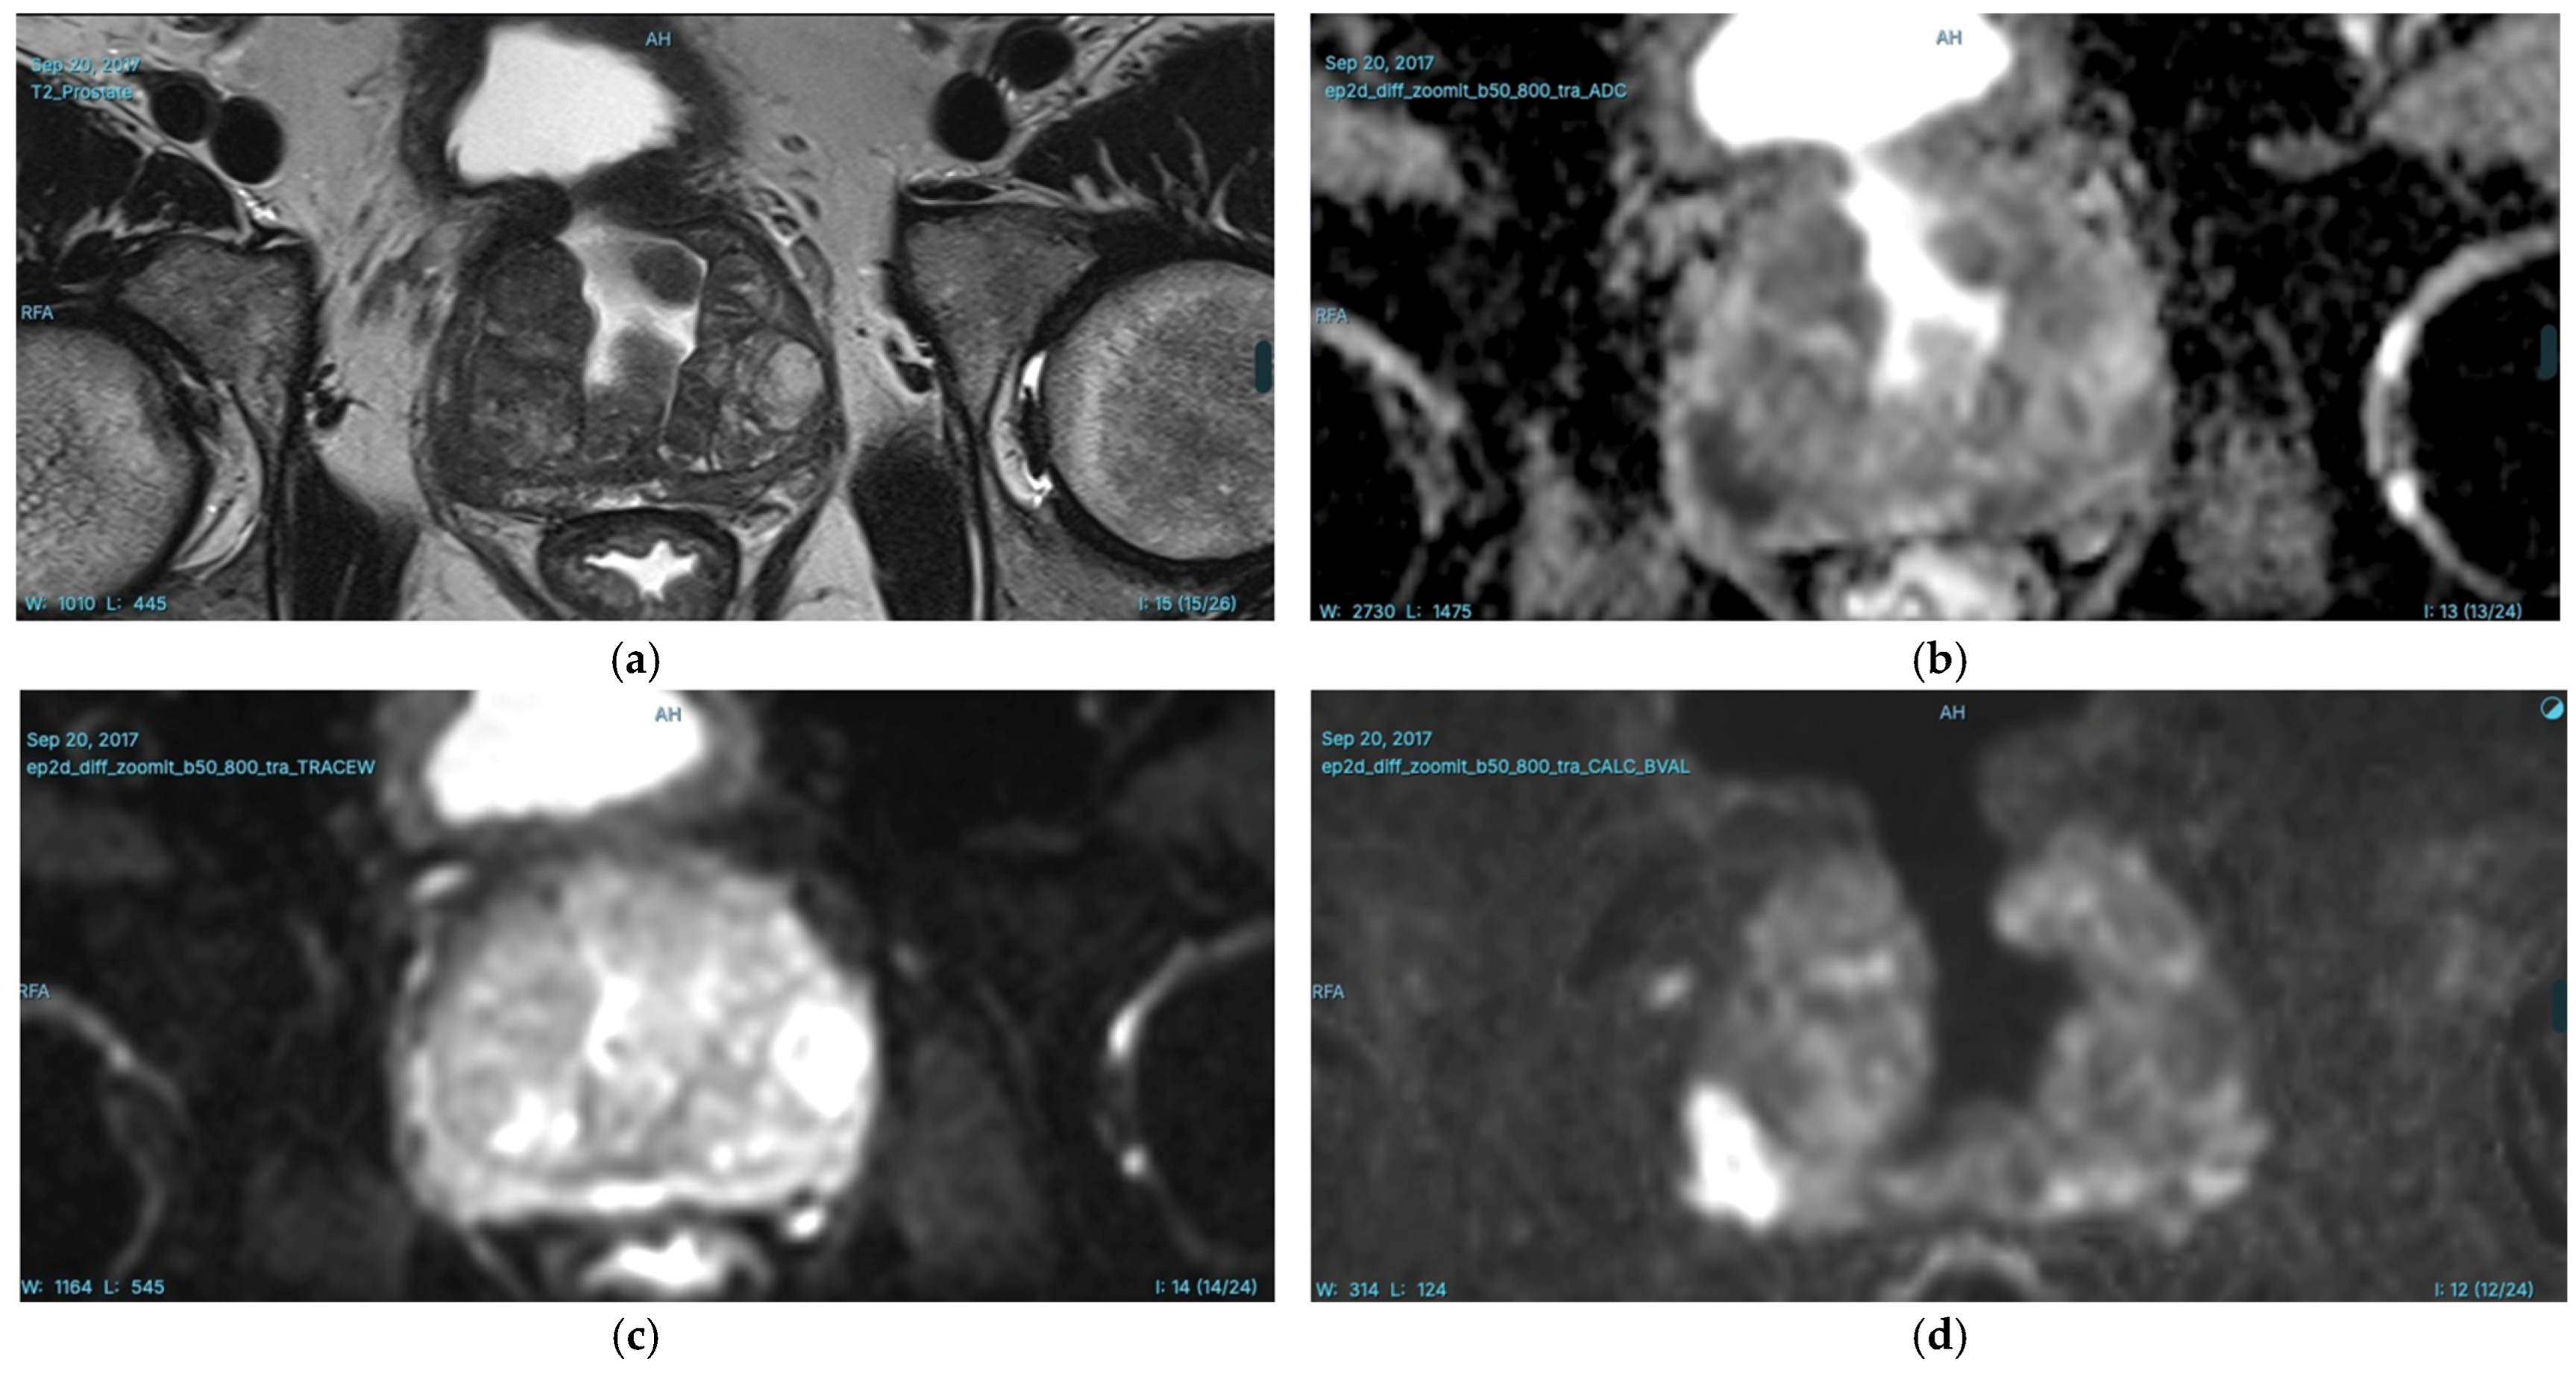

- Hu, L.; Fu, C.; Song, X.; Grimm, R.; von Busch, H.; Benkert, T.; Kamen, A.; Lou, B.; Huisman, H.; Tong, A.; et al. Automated deep-learning system in the assessment of MRI-visible prostate cancer: Comparison of advanced zoomed diffusion-weighted imaging and conventional technique. Cancer Imaging 2023, 23, 6. [Google Scholar] [CrossRef]